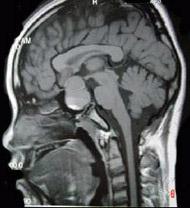

问题 男,47岁,视物模糊数月,头痛、恶心、呕吐3天,行MRI检查如图,最可能的诊断为()

选项 A.颅咽管瘤 B.脑膜瘤 C.垂体瘤并出血 D.蛛网膜囊肿 E.表皮样囊肿

答案 C